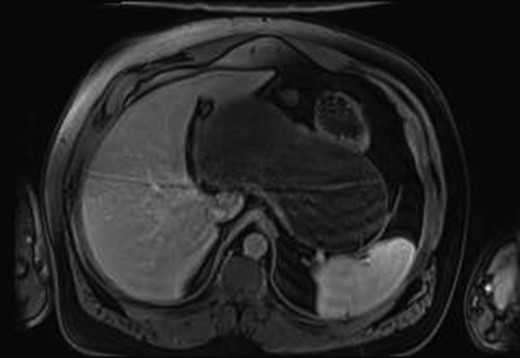

MRI gave a diagnosis of a non-communicating GD (Fig. 1). The PETCT showed a moderately hypermetabolic uptake in the posterior wall of the mass, which could not differentiate a benign or malignant origin. Gastric endoscopy showed an extrinsic compression of the gastric body, with a normal mucosa.

MRI imaging showing a cystic mass located between gastric antrum, pancreas, spleen and hepatic hilum.